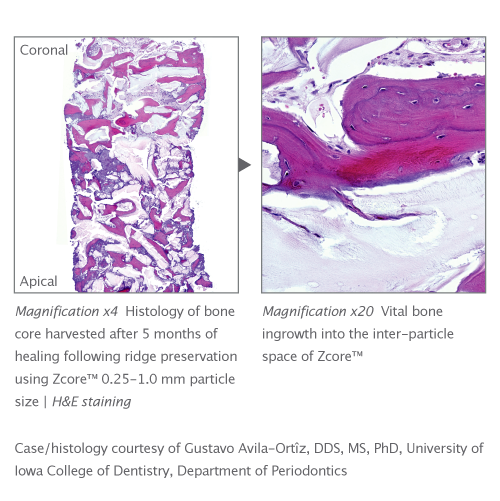

Zcore™ is an osteoconductive, porous, anorganic bone mineral with a carbonate apatite structure derived from porcine cancellous bone. Proprietary processing steps preserve both interconnecting macroscopic and microscopic porous structures of Zcore™ that helps support the formation and in-growth of new bone.

• Interconnecting macroscopic and microscopic porous structure supports the formation and ingrowth of new bone

• 88% to 95% Void Space: hyper-porosity of porcine cancellous matrix and intra-particle space facilitated by rough particle morphology reduce bulk density of the graft, allowing greater empty space for new bone growth